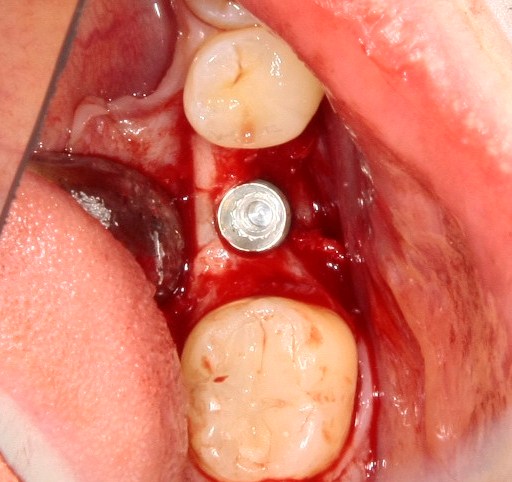

Рекомендации по установке имплантов. Для всех. Часть V.